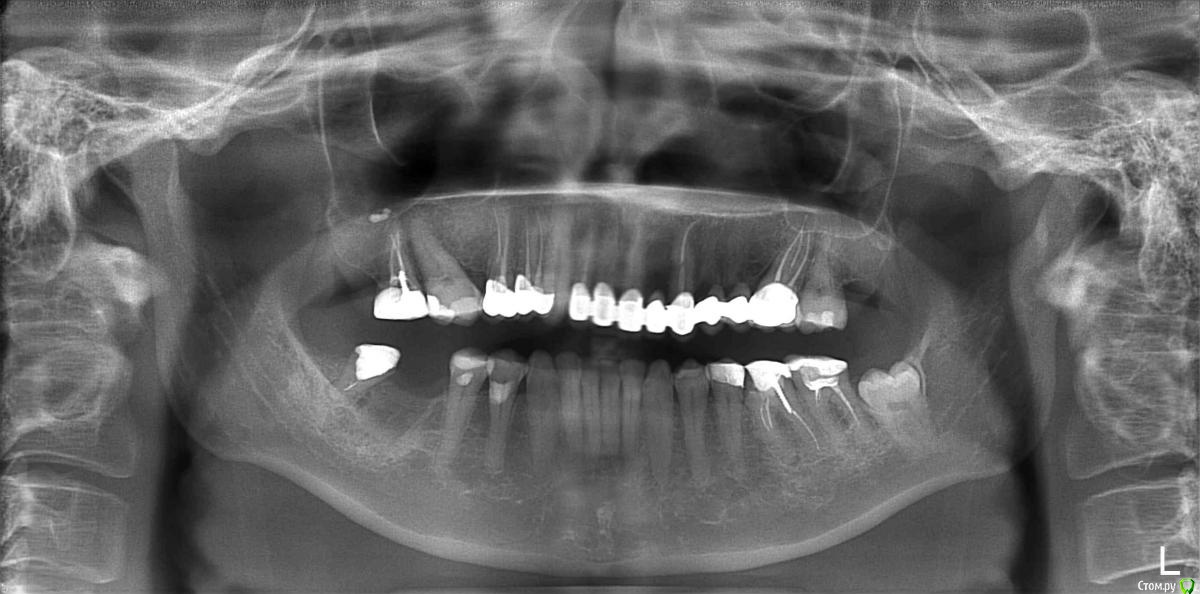

ElenaP. Опубликовано 17 августа, 2018 Поделиться Опубликовано 17 августа, 2018 Уважаемые доктора и специалисты! Помогите, пожалуйста, разобраться, что произошло с моими верхними зубами после установки цельного моста из 8 зубов. 1. Почему ширина всего зубного ряда уменьшилась на почти на 1,5 см, снимок "после" был сделан на той же машине, что и "до". 2. Почему провисло "небо" слева, что это означает? 3. Что за треугольники на снимке "после" в уголках верхней челюсти, похожие на разрез челюсти? Простите, если мои вопросы непрофессиональные, мой доктор считает, что все хорошо, хотя мост пришлось снять из-за сильнейших болей в лице и во рту, разумеется. Прошло более 5 месяцев, до сих пор хожу с временными мостами, но все страшно болит. Спасибо большое. На всякий случай даю снимок оригинальный, до того, как решилась на это безумие. Ссылка на комментарий

kramer Опубликовано 17 августа, 2018 Поделиться Опубликовано 17 августа, 2018 (изменено) 1. Ничего не изменилось. На снимке №2 и 3 в фокус попал еще позвоночный столб, поэтому объекты на снимке №1 кажутся больше. 2. ??? 3. Укажите стрелкой. Изменено 17 августа, 2018 пользователем kramer Ссылка на комментарий

kramer Опубликовано 17 августа, 2018 Поделиться Опубликовано 17 августа, 2018 Что болит, как болит, когда началось, что предпринимали? Нужно больше данных. Ссылка на комментарий

Бендер Опубликовано 17 августа, 2018 Поделиться Опубликовано 17 августа, 2018 Нижний ряд тоже получается ушёл на полтора сантима? Ссылка на комментарий